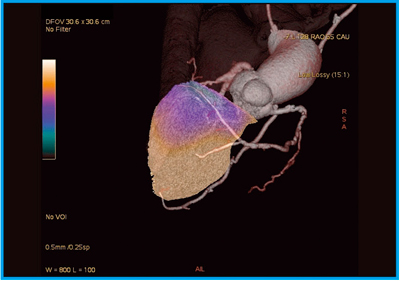

●症例7:肺高血圧症のLung perfusion imaging

肺高血圧症の肺血流シンチグラフィのデータを,CTの3D VR画像に投影表示することで,血流画像を同時に評価する研究を行っている(図11)。血流が低いところは青色,高いところは黄色で表現され,SPECT/CTを用いると肺血流の分布が三次元的に一目瞭然となる。

図11 症例7:肺高血圧症のLung perfusion imaging(開発検討中)